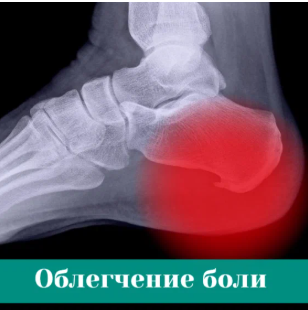

УДАРНО-ВОЛНОВАЯ ТЕРАПИЯ ПРИ ПЯТОЧНОЙ ШПОРЕ

Бесплатно Вы получаете полноценное УЗИ и УВТ при пяточной шпоре. Также в прием входит бесплатная консультация профильного врача высшей категории и процедура.